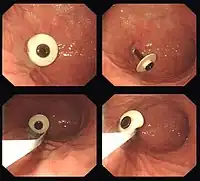

PEG tubes with rigid, fixed "bumpers" are removed endoscopically. The PEG tube is pushed into the stomach so that part of the tube is visible behind the bumper. An endoscopy snare is then passed through the endoscope, and passed over the bumper so that the tube adjacent to the bumper is grasped. The external part of the tube is then cut, and the tube is withdrawn into the stomach, and then pulled up into the esophagus and removed through the mouth. The PEG site heals without intervention.